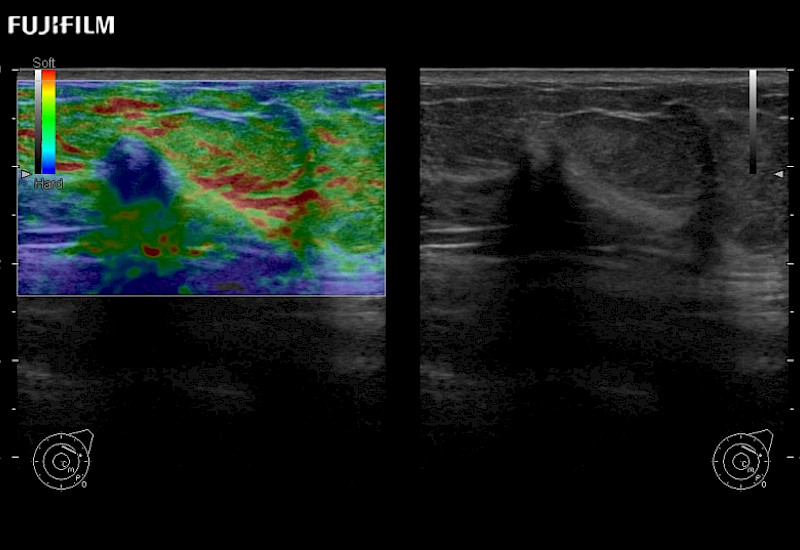

Learn moreFujifilm Healthcare continues to listen to the experts, our neurosurgeons, by developing an ultrasound system specifically designed for the Operating Room.

Guidance is the fundamental purpose for all of our surgical ultrasound technology. Fujifilm Healthcare is committed to designing tools that help neurosurgeons navigate inside the human body and provide the necessary information to immediately make critical surgical decisions.

With the ARIETTA Precision the next level of surgical ultrasound is here.